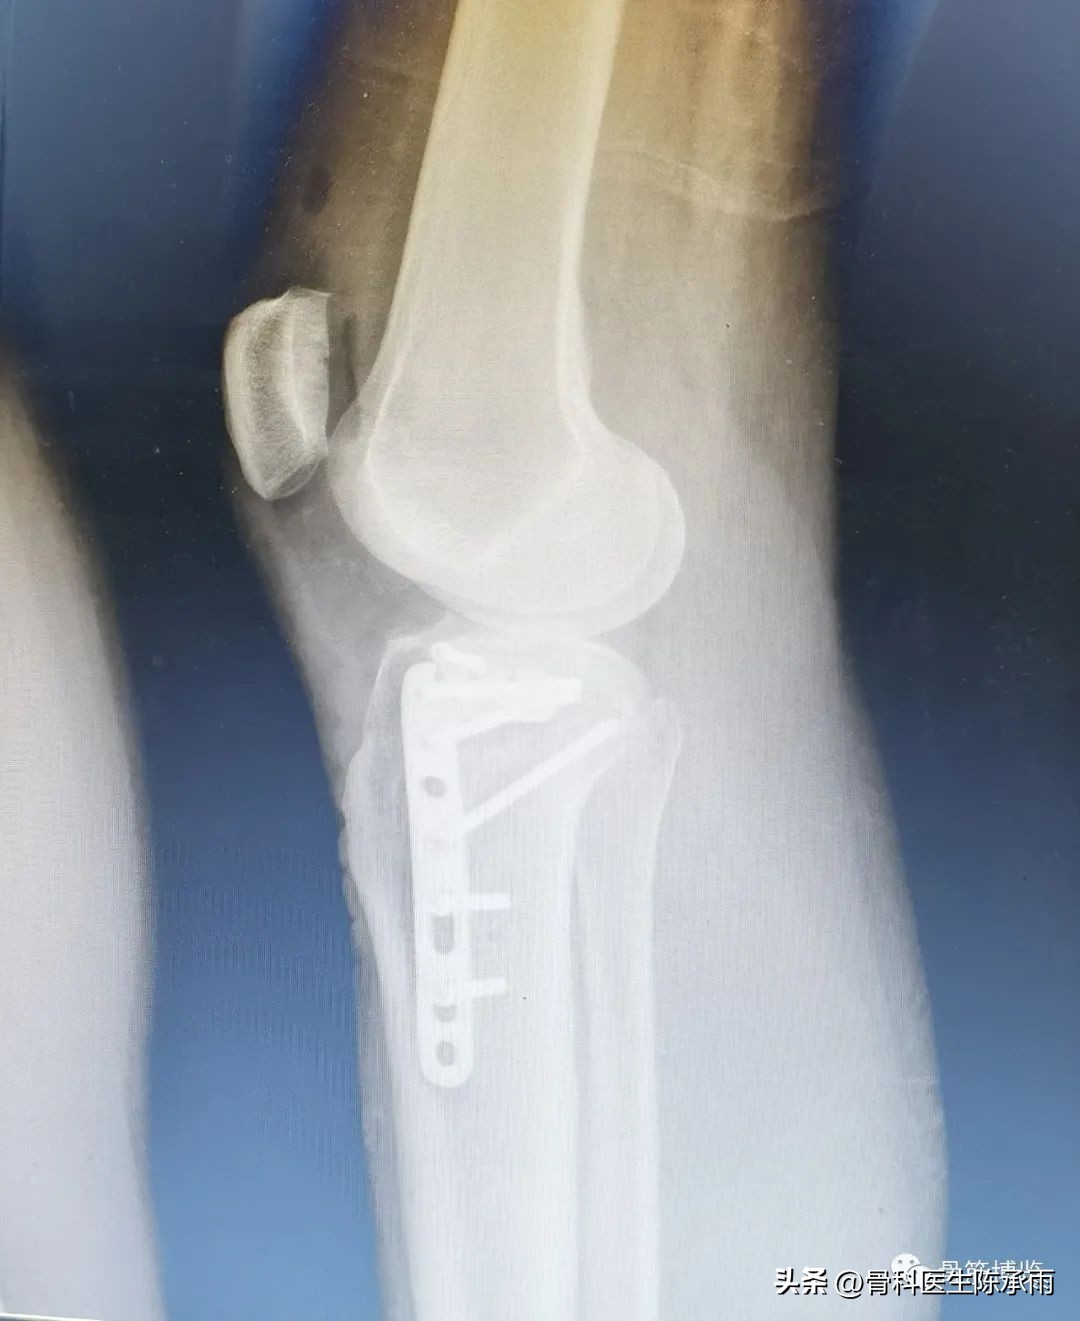

1例

2例

3例

4例

5例

6例

7例